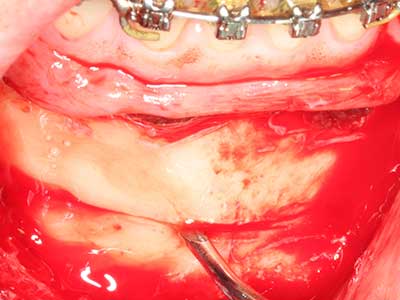

Il tessuto osseo non è semplicemente una struttura minerale, ma contiene anche una percentuale significativa di fibre di collagene. Ciò significa che non possiede solo una buona forza di compressione, ma anche un certo livello di flessibilità che è possibile sfruttare durante l'esecuzione degli accrescimenti di osso. Nella procedura di espansione classica con incisione ossea, la cresta alveolare atrofizzata viene incisa longitudinalmente ed espansa con cautela dopo aver raggiunto una profondità di osteotomia adeguata (figg. 13-16), idealmente senza una sostanziale rimozione del periostio (Brugnami, Caiazzo et al. 2014, Stricker, Fleiner et al. 2014). I sistemi a piastra e vite con distanza di espansione incrementale si sono dimostrati efficaci nella separazione delle due lamelle ossee restando al di sotto della soglia di frattura. In generale, sono richieste larghezze dell'osso residuo di almeno 3-4 mm (Chiapasco, Zaniboni et al. 2006) per garantire un'adeguata flessibilità e una copertura sufficiente dell'osso per gli impianti futuri. Se necessario, un'osteotomia di rilascio verticale su uno o più lati può migliorare la flessibilità. Una combinazione con ulteriori tecniche di accrescimento, in particolare dal lato buccale, è stata descritta come un'alternativa alla tecnica classica.

La procedura di incisione è particolarmente atraumatica e non comporta una perdita significativa di dimensione durante l'utilizzo delle seghe piezoelettriche, così come non si notano differenze rilevanti tra impianti in mandibole incise e impianti in una cresta alveolare senza deficit osseo (Chiapasco, Zaniboni et al. 2006, Danza, Guidi et al. 2009). Una sufficiente irrigazione continua è essenziale, tuttavia, in particolare con incisione profonda e localmente ristretta, per prevenire la sollecitazione termica nelle regioni apicali dell'osteotomia.